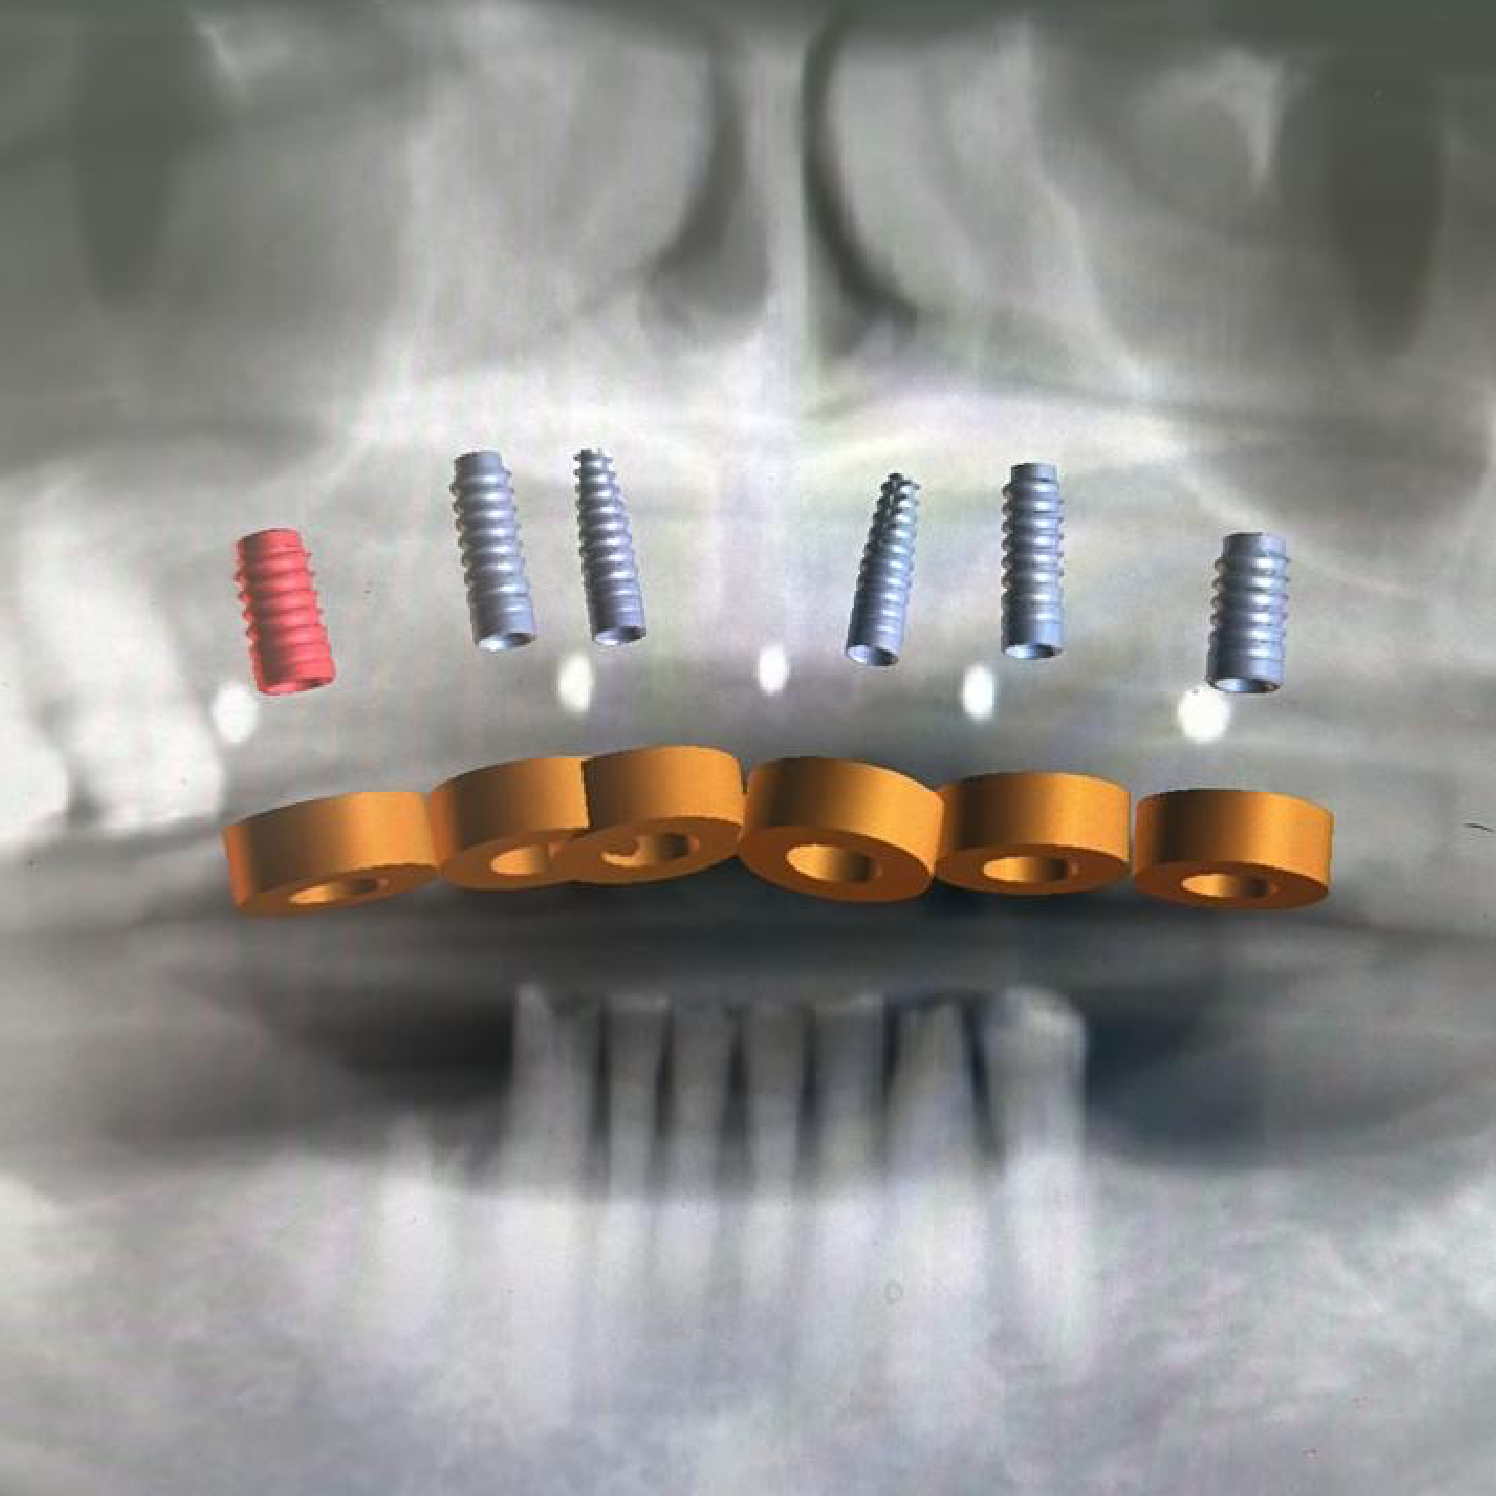

- Evaluación inicial: estudio radiográfico y revisión de salud general.

- Colocación del implante: cirugía ambulatoria para insertar el tornillo en el hueso.

- Periodo de osteointegración: de 3 a 6 meses, el implante se une al hueso.